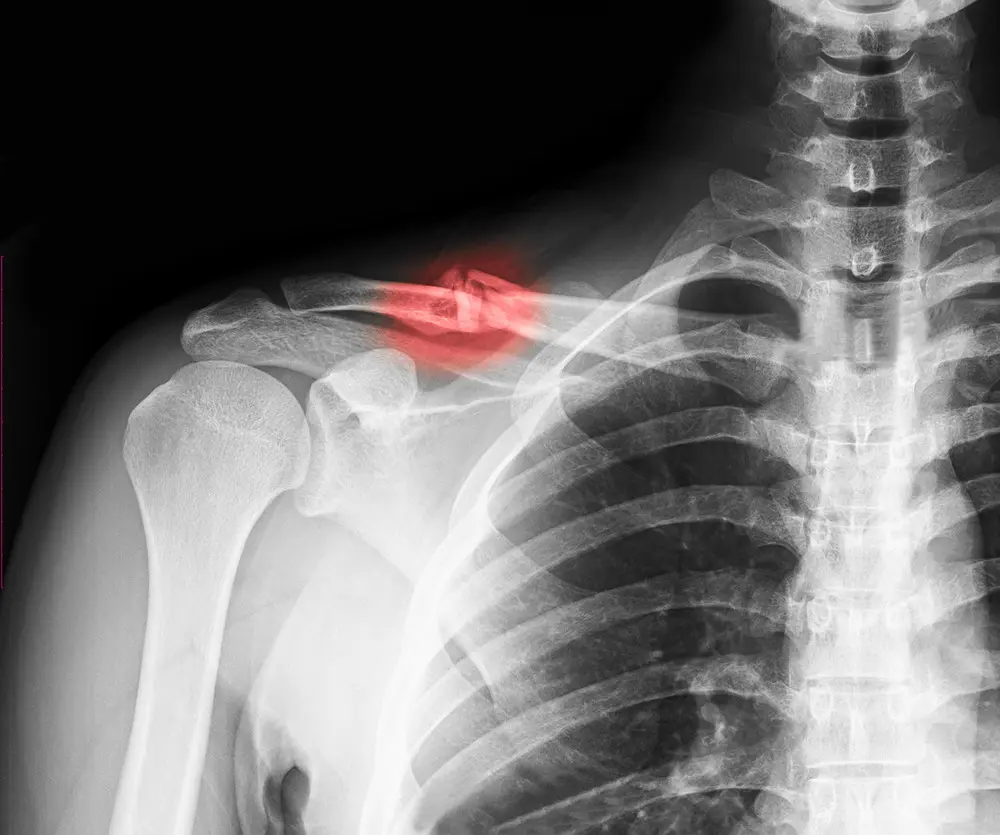

- Determine the type and severity of a humerus fracture and identify associated shoulder or elbow injuries